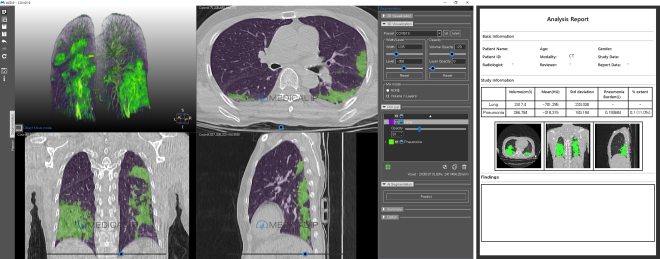

▲MEDIP COVID19를 실행한 모습

AI 의료영상 분석 플랫폼 및 의료용 3D프린팅 전문기업 메디컬아이피가 CT 영상을 활용해 코로나 폐렴 증상을 정량화 할 수 있는 소프트웨어 ‘MEDIP COVID19‘을 전 세계에 무료로 배포한다고 지난 18일 밝혔다.

회사 측은 “한중 코로나 환자의 익명화 된 의료데이터를 활용해 코로나19에 특화된 AI 기술을 개발했다”며, “이 기술로 환자의 CT 영상을 분석해 1분 내외로 코로나 폐렴을 자동으로 탐지, 분할, 정량화 할 수 있다“고 설명했다.